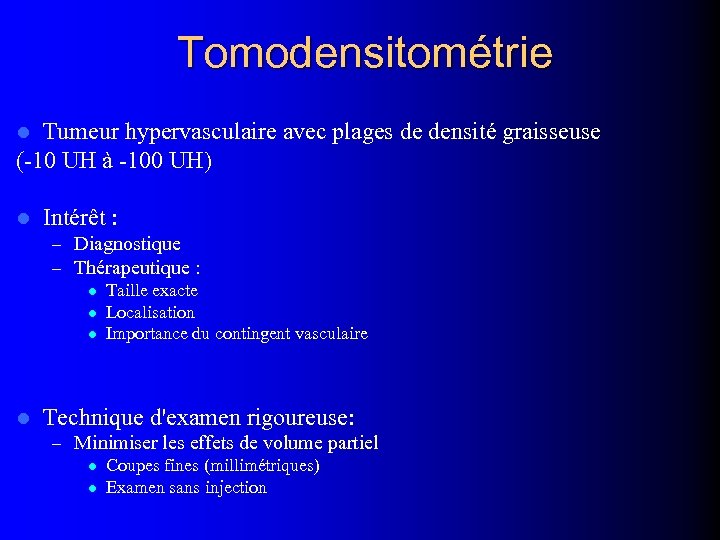

Tomodensitométrie Tumeur hypervasculaire avec plages de densité graisseuse (-10 UH à -100 UH) l l Intérêt : – Diagnostique – Thérapeutique : l Taille exacte l Localisation l Importance du contingent vasculaire l Technique d'examen rigoureuse: – Minimiser les effets de volume partiel l Coupes fines (millimétriques) l Examen sans injection

Tomodensitométrie Tumeur hypervasculaire avec plages de densité graisseuse (-10 UH à -100 UH) l l Intérêt : – Diagnostique – Thérapeutique : l Taille exacte l Localisation l Importance du contingent vasculaire l Technique d'examen rigoureuse: – Minimiser les effets de volume partiel l Coupes fines (millimétriques) l Examen sans injection